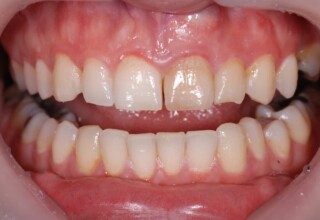

Δυσχρωμικοί άνω πλάγιοι τομείς

Οι όψεις πορσελάνης είναι ο καλύτερος τρόπος αντιμετώπισης αισθητικών προβλημάτων στην πρόσθια περιοχή του στόματος. Συνδυάζουν συντηρητική αφαίρεση οδοντικής ουσίας και πολύ υψηλή αισθητική απόδοση. Στο παρακάτω εκτεταμένο περιστατικό υπήρχαν: παλαιά σφραγίσματα, δυσχρωμίες, κακό σχήμα και μήκος δοντιών, κακή αναλογία δοντιών-ούλων. Έγινε προσεκτικός εργαστηριακός σχεδιασμός σε εκμαγεία απ’όπου προέκυψαν προσωρινές όψεις που τοποθετήθηκαν στο στόμα για δοκιμή και διορθώσεις. Όταν οριστικοποιήθηκαν οι μετατροπές, οι προσωρινές χρησιμοποιήθηκαν σαν οδηγός για τις μόνιμες. Οι πέντε μόνιμες όψεις πορσελάνης που κατασκευάστηκαν για τα πέντε πρόσθια δόντια της άνω απεκατέστησαν σχεδόν άψογα την αισθητική εμφάνιση της ασθενούς.